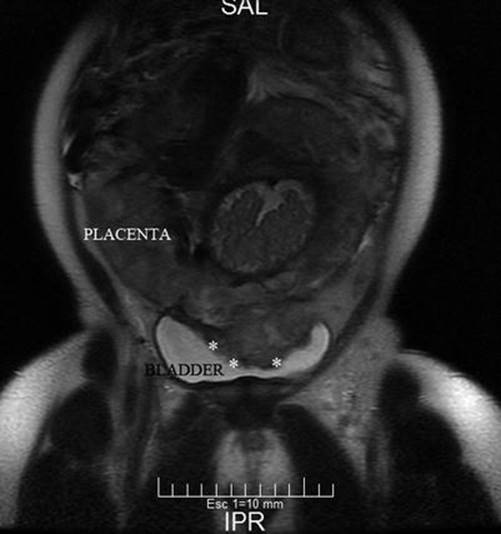

Fig. 14.13

Coronal MRI T2 image: white arrows, massive bladder invasion by AIP type 2 (percreta). Notice that placenta is lobulated. Naturally liquid contrast of bladder allows the proper identification of newly formed vessels, given their hypointense signal. PI parametrial invasion

Anterior AIP is the most common location worldwide, because it is also the most common site of the previous scar (caesarean). However, the lateral part of the uterus (parametrium) could not be seen properly by US due to the lack of natural contrast or liquid. But in recent years, some studies have investigated the possibility to explore the parametrial area in cervical cancer [23, 24]. Although parametrial invasions are not common in all countries, it is a condition relatively frequent associated after unsafe abortions. This variety must also be suspected in cases of lateral retained placenta, curettage by aberrant cotyledon or by curettage after short-time caesarean interval [11]. Coronal and axial slices of pMRI are really accurate (Figs. 14.7 and 14.8) to demonstrate this kind of invasion [13]. As it was commented before, lateral invasions may have two subtypes: (1) There is a lack of support of myometrium, because it appears thin. The placenta clearly protrudes until the lateral pelvic wall. (2) Besides placenta protruding (lateral bulging) a vascular signal of engorged vessels is evident around the invasion. The last type of invasion is very rare, though highly problematic to solve. Although other invasions are suitable to leave the placenta in situ, this is particularly dangerous in parametrial invasion type 2. Postpartum uterine contractions may produce an unexpected laceration of the weak lateral myometrium and start a massive haemorrhage. An emergency scenario includes a patient with a severe hypovolaemic shock, intra-abdominal or retroperitoneal bleeding and invaded placenta in a deep space plenty of enlarged vessels, which is a true surgical nightmare [25]. Except for a few special cases, this episode is the cause of death, because it is almost impossible to solve all problems very quickly. Although these cases are not reported or published, the specialist knows about them through informal talking with other specialists in congresses.

Fig. 14.7

Coronal T2 image: MRI was requested by US doubt of anterior invasion (black asterisk). Parametrial invasion (PI) was evident in the right side of the uterus. After study, the patient admitted having an abortion